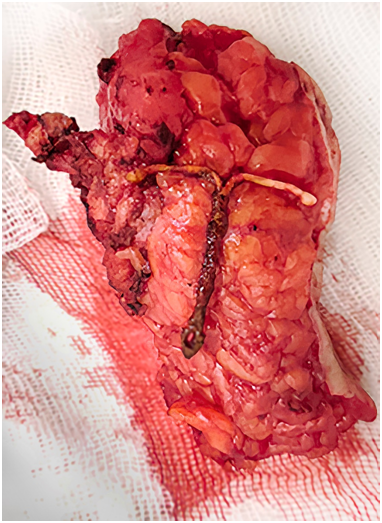

09.10.2025 г. выполнена операция: свищ маркирован метиленовым синим, методом прогрессивного расширения произведено его иссечение. В животе обнаружена внутриматочная спираль (рис. 3). В области вмешательства наблюдался спаечный процесс, отграничивающий свищ от свободной брюшной полости. Кишечного отделяемого не было. При тугом наполнении мочевого пузыря 0,9% раствором натрия хлорида с метиленовым синим поступления в операционную рану не отмечалось. Объем выведенного маркера соответствовал введенному в мочевой пузырь (проба Зельдовича). Рана санирована, ушита с оставлением марлевого выпускника.

Рис. 3. Макропрепарат: иссеченный фрагмент передней брюшной стенки со свищем и внутриматочной спиралью

Fig. 3. Macroscopic view of excised fragment of the anterior abdominal wall with fistula and intrauterine contraceptive device